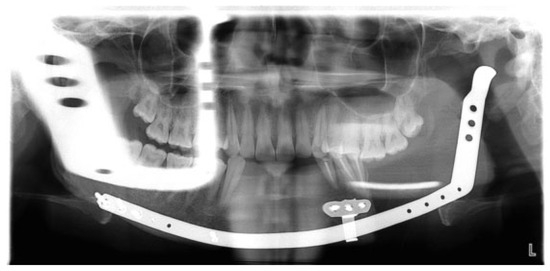

Mandibulo-maxillary fixation (MMF) screws are inserted into the bony base of both jaws in the process of fracture realignment and immobilisation. The screw heads act as anchor points to fasten wire loops or rubber bands connecting the mandible to the...